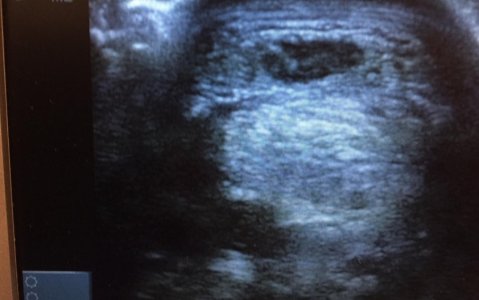

I see a face!An ultrasound this time.

Wow that's really interestingBlack holes on a scan have IME meant damaged suspensories, but I might be well off track on that.

Tumour? Ruptured Tendon? Not so sureShall we go to feet? I have lots of different kinds of feet pics!

As for the foot one foreign body?

Hmmm keratoma?Not quite.